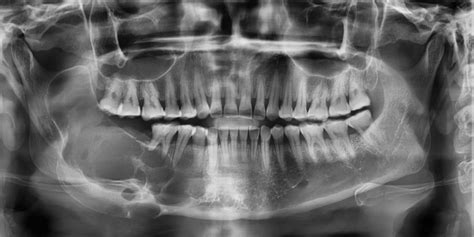

En odontología, algunas afecciones pueden pasar desapercibidas durante meses si no se detectan en una revisión. Generalmente es necesario realizar una radiografía para diagnosticar esta patología que se manifiesta a través de una zona oscura en el hueso.

El principal método para detectar un quiste maxilar es a través de una radiografía, en la que se puede observar una mancha de color oscuro en el hueso. En la ortopantomografía (radiografía en 2D de toda la boca) el quiste maxilar se observa como una zona oscura y redondeada en forma de bolsa.

Una vez que el dentista sepa de la presencia del quiste, es posible que solicite pruebas adicionales, tales como una tomografía computarizada o una biopsia, que le permitan tener una información más completa y detallada sobre el tipo de quiste, la extensión del mismo y sus características. Para poder diferenciar un quiste de otro tipo de lesiones, el dentista debe tener en cuenta los síntomas que presenta el paciente, así como la ubicación del quiste.